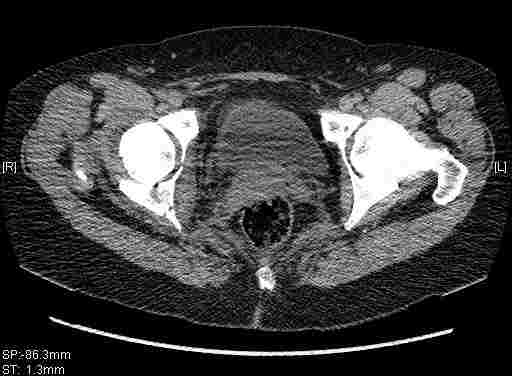

Удалось сегодня вывести пациентку в соседнюю больницу, где есть кт. Срезы сделаны только горизонтальные.

|

Приветствую,Антон.Рункова рядом нет,но после полученных данных КТ,обсуждали совместно.Итог обсуждения-развернутый ответ дать не получится,т.к.срезы выбраны не информативные.Если ориентироваться на данные 3D,то ,ИМХО,можно лечить на вытяжении.